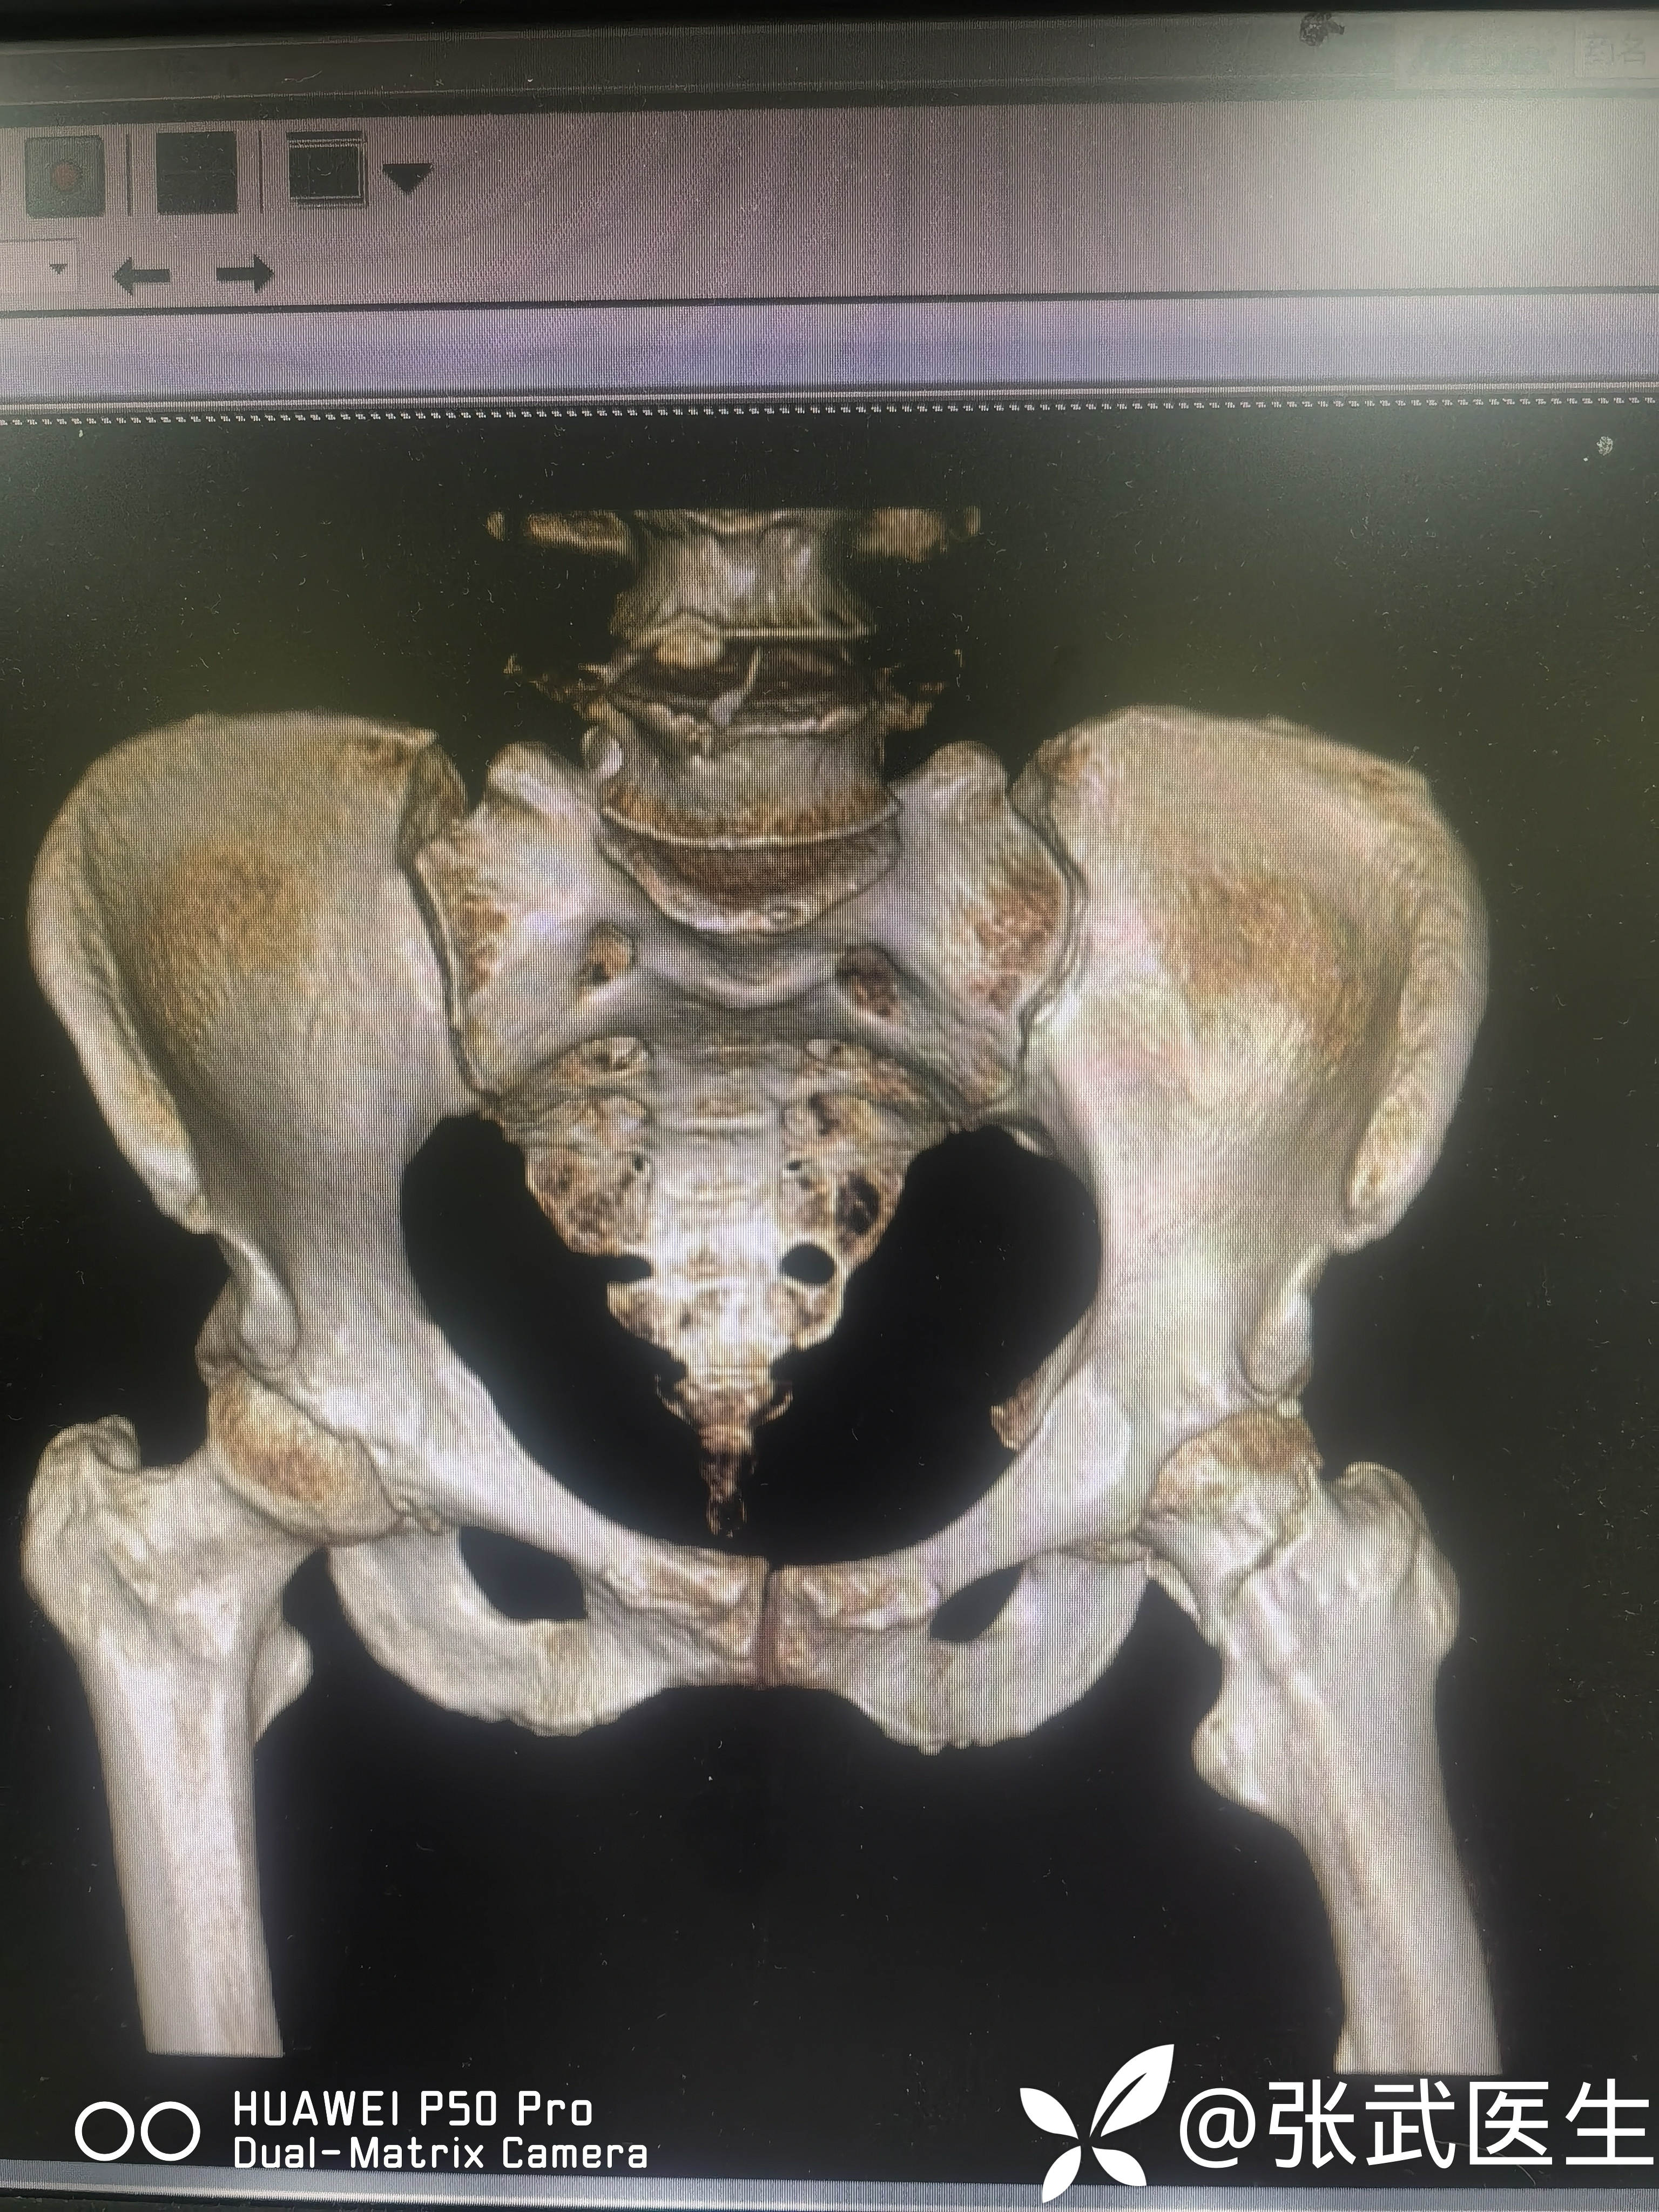

诊断:左股骨颈骨折 Garden II型

术前:

pauwels>50度